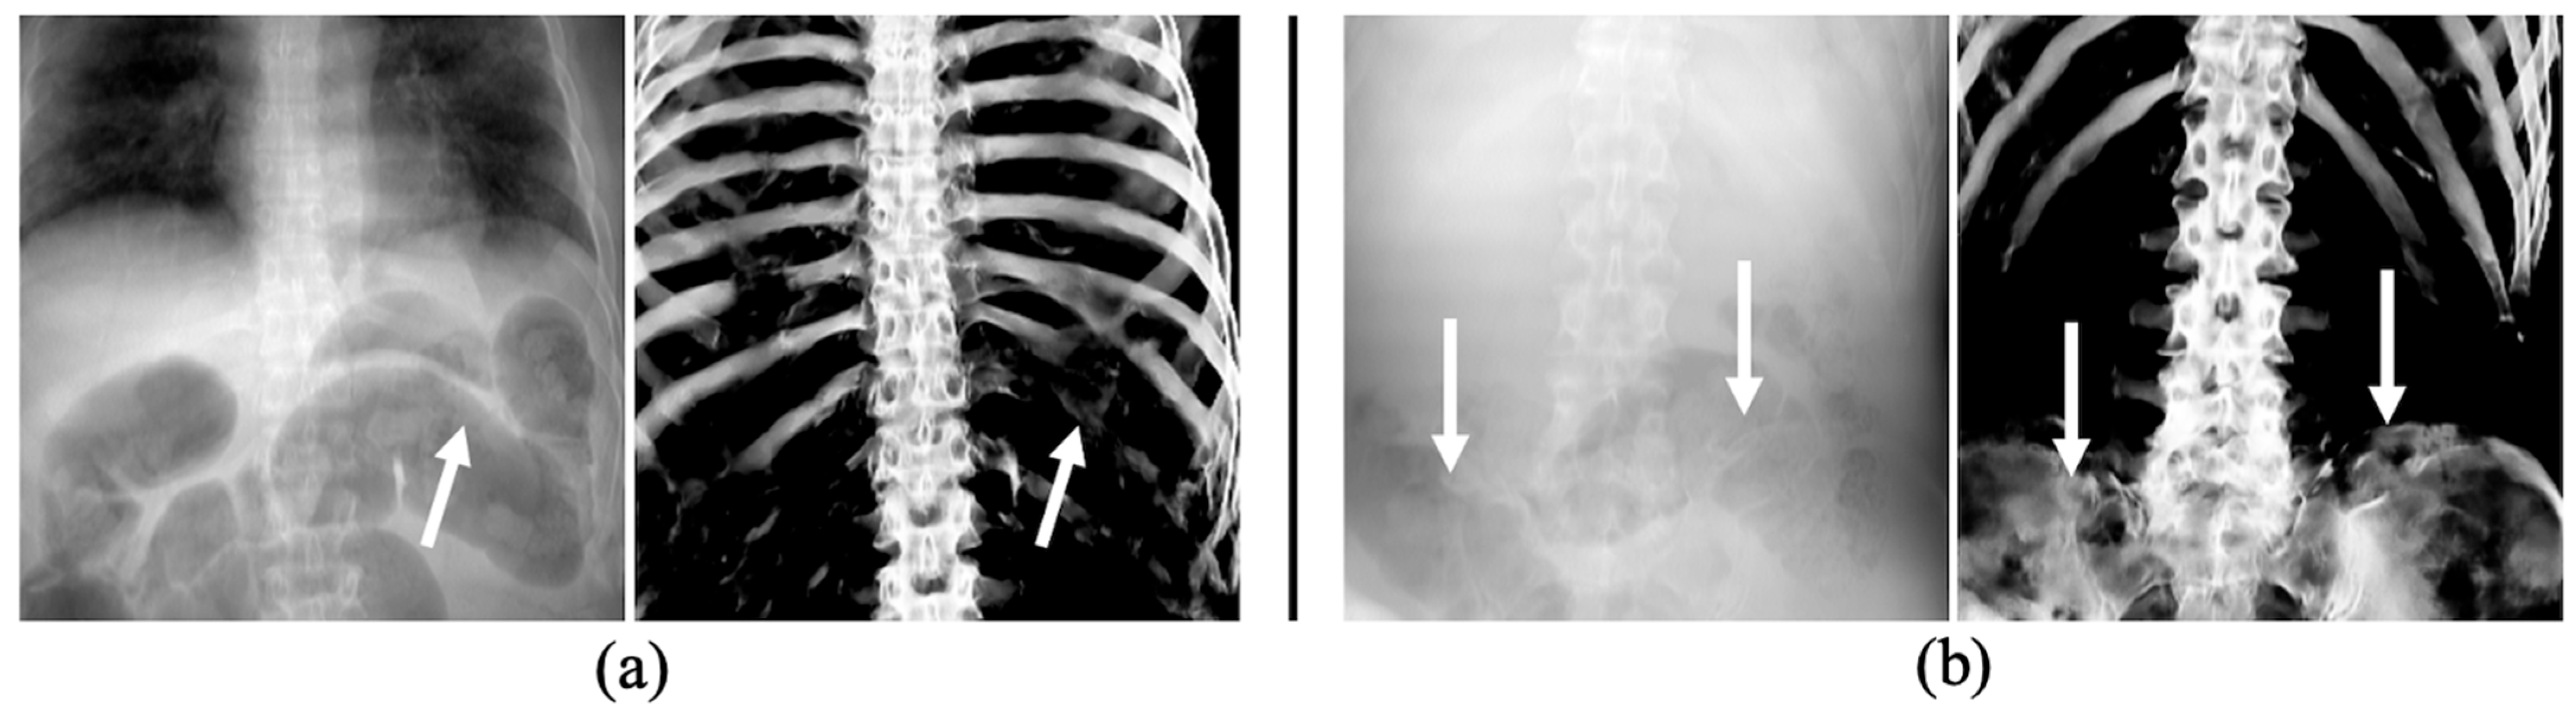

3.3. The Performance of Bone Extraction on Real 2D X-ray Images (CXRs)